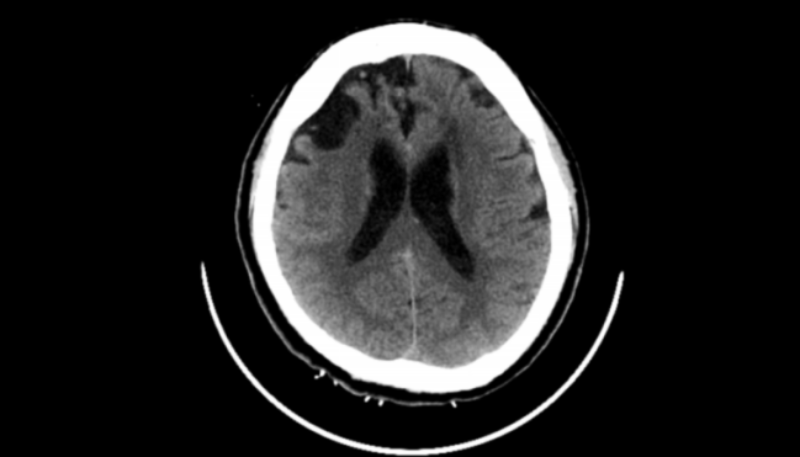

醫(yī)生團隊在患者頭上畫好線,找準位置錐顱,置管進入,有淡紅色的血水從管子里流出來。固定好引流管后,連接上引流裝置。隨后根據(jù)腦里血腫的情況,每天往里面打一到兩次尿激酶,每次用的量在 5000 單位到 20000 單位不等。一直到血腫基本清除了,才把引流管拔掉。

軟通道管道置入后